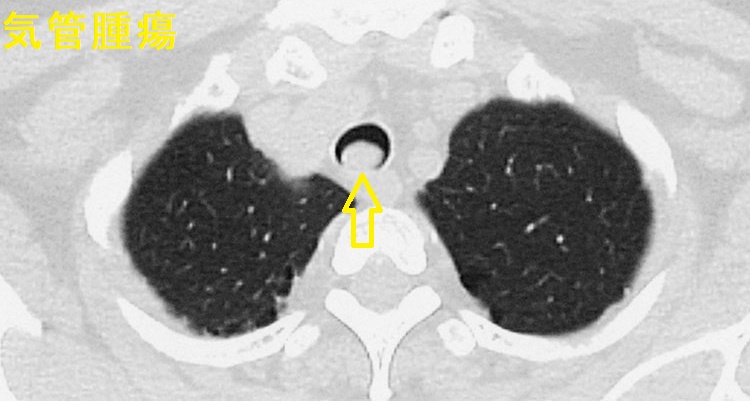

非常にまれですが、気管内の異所性甲状腺で

- 吸気時喘鳴(ストライダー)[Indian J Otolaryngol Head Neck Surg. 2019 Oct;71(Suppl 1):276-278.]

- 日和見感染としてムコール甲状腺炎[Ann Acad Med Singap. 2022 Mar;51(3):189-191.]

をおこした報告あり。